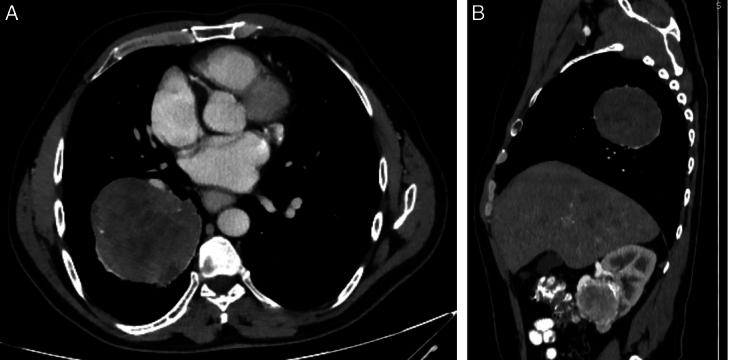

CASE PRESENTATION

The authors report a case of a 51-year-old male patient with renal cell carcinoma. During his evaluation, he seemed to have a lung mass which revealed to be a carcinoid tumour. As the patient had two primary malignancies, he was managed according to the treatment options for each tumour.

病例介绍

作者报告了一例51岁男性肾细胞癌患者。在对他进行评估期间,他似乎有一个肺部肿块,结果显示为类癌肿瘤。由于该患者患有两种原发性恶性肿瘤,因此根据每种肿瘤的治疗方案对他进行了处理。